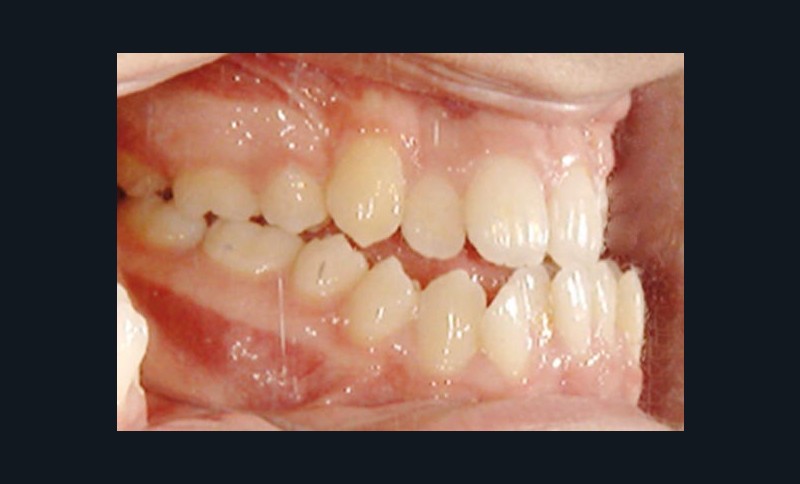

Olivier se présente à l’âge de 12 ans avec une classe III squelettique à prédominance mandibulaire, accompagnée d’une hyperdivergence et d’une endomaxillie responsable des inclusions des canines supérieures à forte obliquité. Une phase d’expansion est réalisée afin de permettre une augmentation du périmètre de l’arcade et la verticalisation des germes des canines. L’expansion permet en effet une normalisation transversale mais ne permet pas de réaliser la mise en place des canines. Les extractions des prémolaires sont alors effectuées et une préparation primaire de l’arcade supérieure par multi-attaches avec désinclusions et tractions des canines est réalisée.